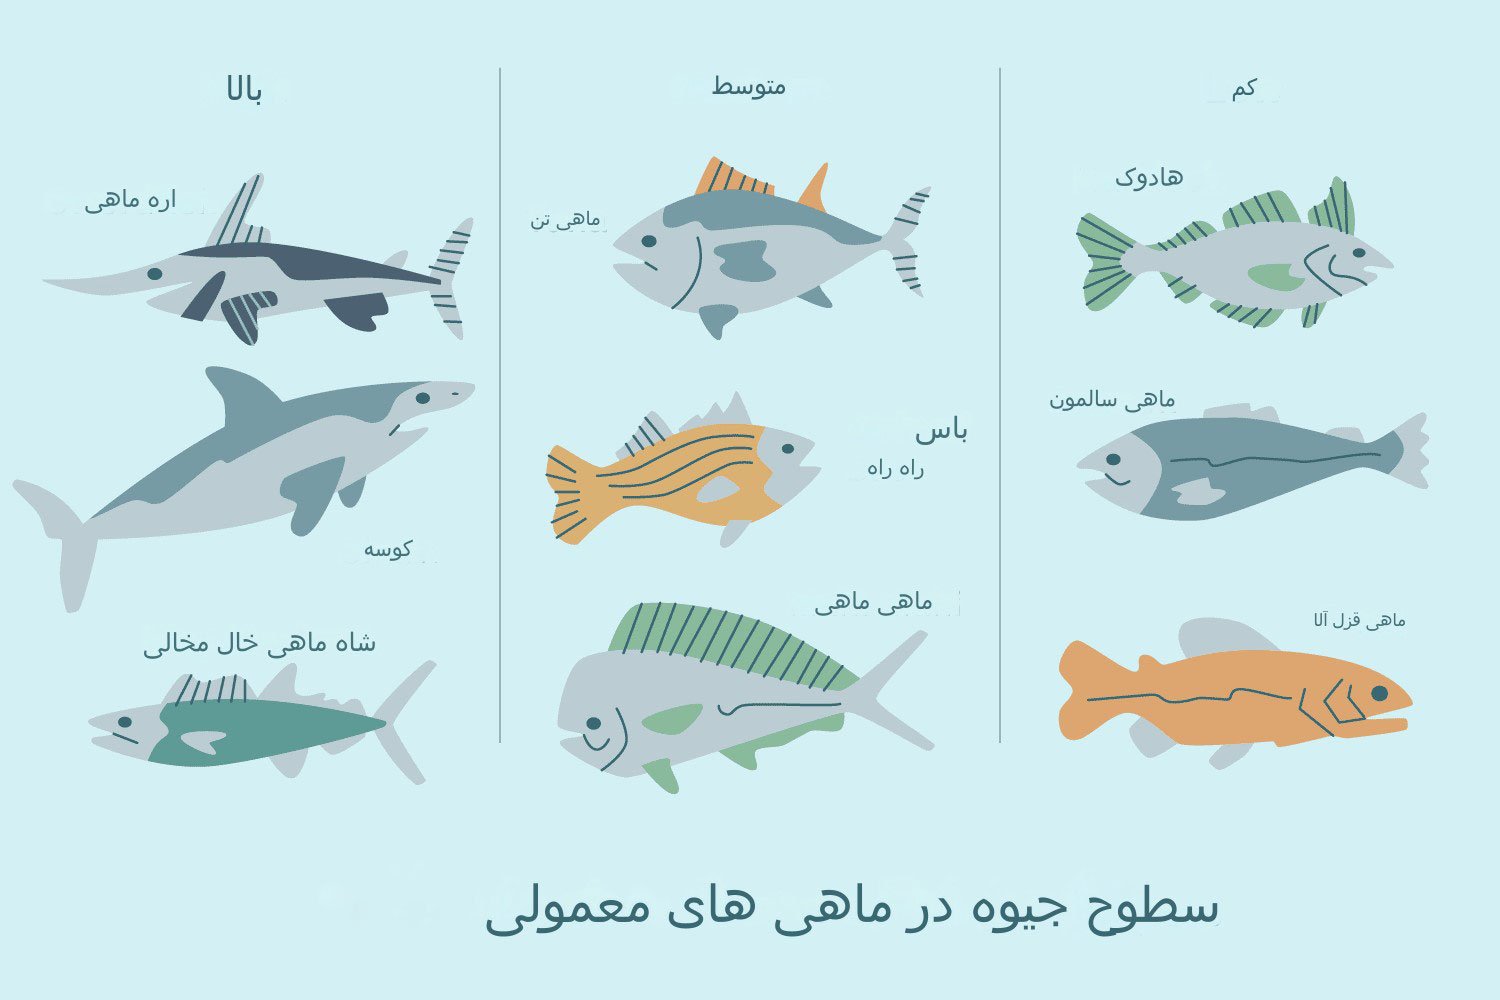

غذاهای دریایی پخته شده منبع خوبی از اسیدهای چرب امگا 3 هستند که یک ماده مغذی مهم برای بارداری شماست. اما باید از ماهی های خاصی اجتناب کرد زیرا سطح جیوه بالایی دارند. ماهی تن، شاه خال مخالی، مارلین، نارنجی رافی، کوسه، اره ماهی، یا کاشی ماهی نخورید. ماهی تن سفید (albacore) را به 6 اونس یا کمتر (170 گرم یا کمتر) در هفته محدود کنید.

همچنین ماهی هایی که در رودخانه ها یا دریاچه های محلی صید می شوند به دلیل مواد شیمیایی موجود در آب می توانند ناسالم باشند. بهتر است از خوردن ماهی صید شده در محل خودداری کنید مگر اینکه بتوانید اطلاعات ایمنی محلی را بررسی کنید. در غیر این صورت، بیش از 6 اونس (170 گرم) از آن را مصرف نکنید و در صورت خوردن آن به میزان 170 گرم، از خوردن ماهی های دیگر در آن هفته خودداری کنید (نکته بسیار مهم و حایز اهمیت).